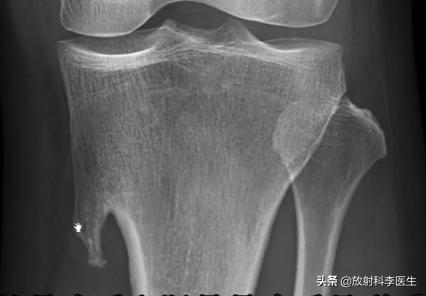

X线表现:1.肿瘤包括骨性基底和软骨帽两部分。骨性基底表现为局限骨凸起,以蒂或宽、窄的基底与母体骨相连。

2.发生在长管状骨的多背离关节生长,病灶的骨皮质及骨松质均与母体骨相延续。病灶顶端呈菜花状或丘状隆起。软骨帽在X线上不显影。软骨钙化时,可见点状或环形钙化灶。

外生骨软骨瘤:胫骨上端内下缘

外生骨软骨瘤(外生骨疣):胫骨上端内下缘